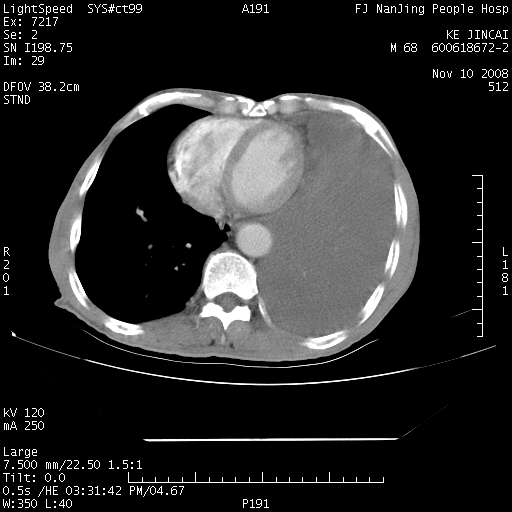

是个很有看头的病例,咋人气那么不旺?没多少人兴趣呢?这个病例几大怪:1   恶性肿瘤侵犯心肌左房怪,心肌一般不会被恶性肿瘤侵犯吧?2   左下肺均匀实变怪,内无含气,有别一般不张实变,含气肺泡完全为液体取代,而非一般不张实变的肺萎陷,冷不丁还以为是肿大的脾脏3   肿瘤本身怪,像tb肺不张4   这么有看头的病例没人气怪。呵呵。

左肺恶性肿瘤侵犯肺动脉,左心房内瘤栓,胸膜转移。